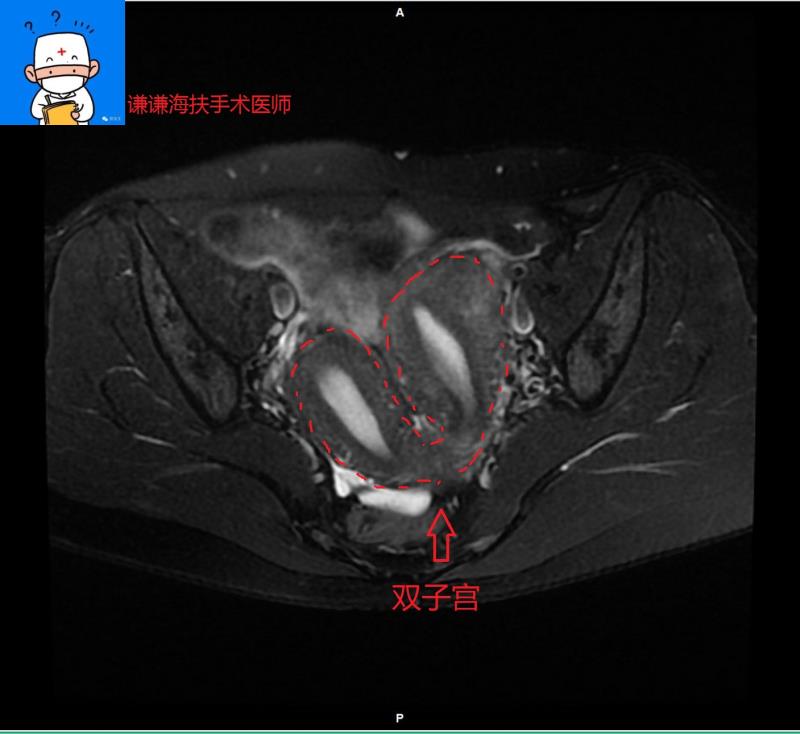

7、子宫肌瘤VS子宫畸形:特别是发育不完全的双子宫,很有可能把另一个子宫当肌瘤处理了。一般通过超声能够鉴别。